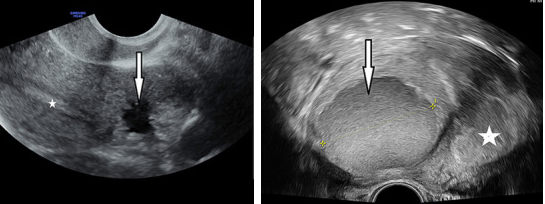

7

Ultrasound images of accessory cavitated uterine malformation (arrows), with uterine cavity denoted by star.25